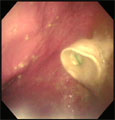

レントゲンにて胃内に円形の異物確認 内視鏡にてペットボトルのキャップ確認 摘出したペットボトルのキャップ

経過:一般状態良好。腹部レントゲンにて胃内にペットボトルのキャップと思われる円形の異物を確認した。胃の大きさに比べてかなり大きく吐き出させるのは困難と判断した。24時間絶食後、全身麻酔下にて胃内視鏡検査を施行した。ただちに白いペットボトルのキャップを確認できたが、通常の把持鉗子でも、バスケット鉗子でも、摘出不能であった。最も大きな把持鉗子を用いてやっと噴門を通過できたが、食道に滞留してしまった。外科用の長い鉗子を経口的に挿入して内視鏡観察下に直接把持して咽喉頭部分を通過させた。処置時間は4時間19分もかかってしまった。翌日、無事退院。

コメント:通常の内視鏡処置の限界と思えるほどの大きさでした。異物に角がないので、噴門・咽喉頭部分にかなりの抵抗がありましたが少々強引に引っ張りだしました。開腹手術移行も頭をかすめましたが、内視鏡医の意地で摘出しました。